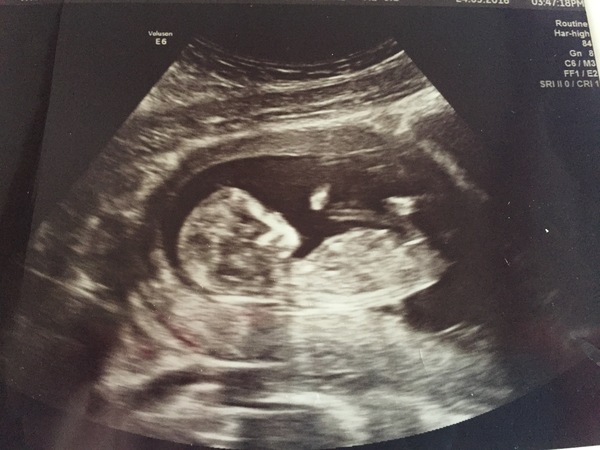

Morning ladies, I've also been AWOL for a while due to work, so it's lovely to catch up on how everyone is doing. Hope all those in pain feel better soon! Got my 16 wk appointment on Tuesday, which is exciting. Hoped my nausea would have gone by now but it's still lingering! I love trying to guess what we're having and change my mind everyday - would anyone like to guess?

Any thoughts on mine? I can't wait to find out at 20 week scan - 3 weeks to go.